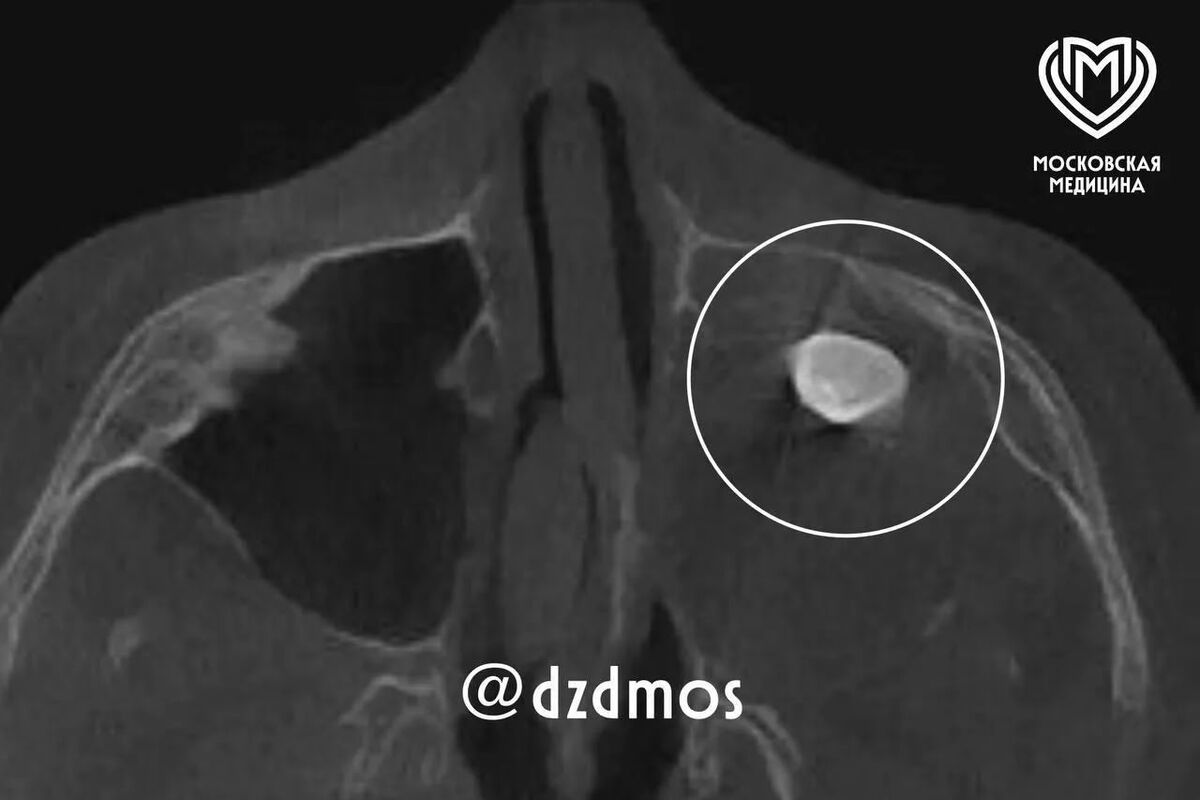

Врачи Филатовской больницы в Москве удалили подростку зуб, который вырос в носу. Об этом сообщает столичный депздрав в своем канале в Max.

Уточняется, что 15-летний мальчик попал в больницу с жалобами на асимметрию лица и заложенность носа. До этого, как отметили в депздраве, мальчика осматривали врачи частной клиники — они нашли в гайморовой пазухе сформировавшийся зуб и предложили удалить его.

Родители подростка решили выслушать второе мнение и обратились за консультацией в Филатовскую больницу, где по результатам консилиума врачи предложили провести операцию по Колдуэллу-Люку, то есть обеспечить доступ через верхнюю десну, чтобы вернуть ему возможность нормально дышать.

Сделав разрез, врачи обнаружили новообразование, внутри которого и находился зуб, рассказал хирург-оториноларинголог Вугар Достиев. По его словам, доброкачественная опухоль оказалась тератомой — эмбрионально-клеточным новообразованием, внутри которого могут находиться элементы тканей, несвойственные этому участку тела.

Достиев уточнил, что после восстановления функций подростка выписали с хорошим самочувствием, также постепенно асимметрия его лица и заложенность носа полностью исчезли.